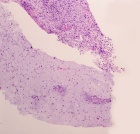

J.S. - 12 year old boy c/o right knee pain and swelling for ten days. Painful at rest, worse at night and with activity. Able to ambulate with pain. Initially the pain was accompanied by fever, chills, malaise, nausea and vomiting; all of which have resolved.